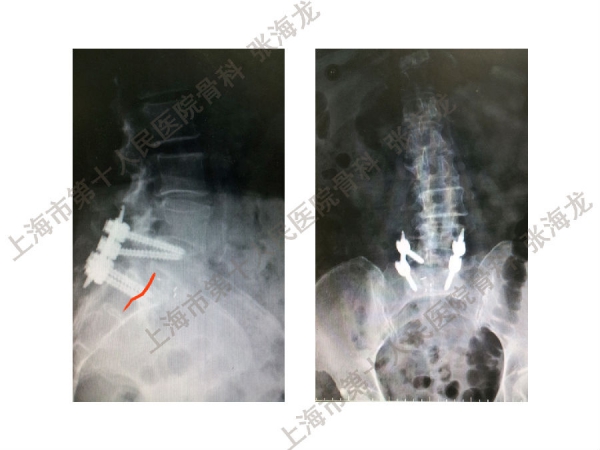

2008年3月至2010年8月,上海市第十人民医院骨科随访49例腰椎滑脱症(峡部裂型和退变型)患者,对比23例微创手术MIS-TLIF和26例开放手术治疗腰椎滑脱症的临床及影像学结果,进行了回顾性研究。

研究发现,Wiltse入路Mis-TLIF更直接的暴露峡部及关节突,对脊柱稳定性的影响较小;彻底松解辅助双重提拉复位Mis-TLIF,对于峡部裂型滑脱有较好的复位效果;对于峡部裂型滑脱,提拉复位在影像学参数上有一定优势;与原位融合相比,ODI.VAS.JOA无明显差异(样本量有限);对于退变性滑脱,单纯撑开椎间隙与原位融合可以获得较好疗效。